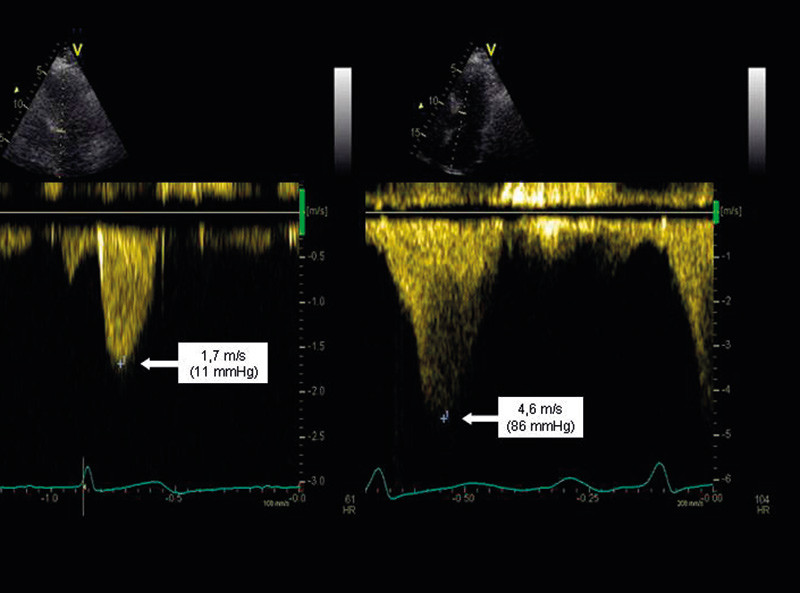

Rekoarktasjon kan beregnes ved bruk av ekkodoppler, og trykkfall på > 20 – 30 mm Hg i hvile er anbefalt som intervensjonsgrense (36). Ved lavere trykkfall i hvile kan ergometrisk stressekkokardiografi benyttes for å påvise restenosens betydning under fysisk arbeid. 50 mm Hg benyttes da som en fleksibel grense. Imidlertid er det like viktig å vurdere hvorvidt det foreligger «diastolisk hale» (fig 4) (37), noe som kan tyde på at koarktasjonen har hemodynamisk betydning.